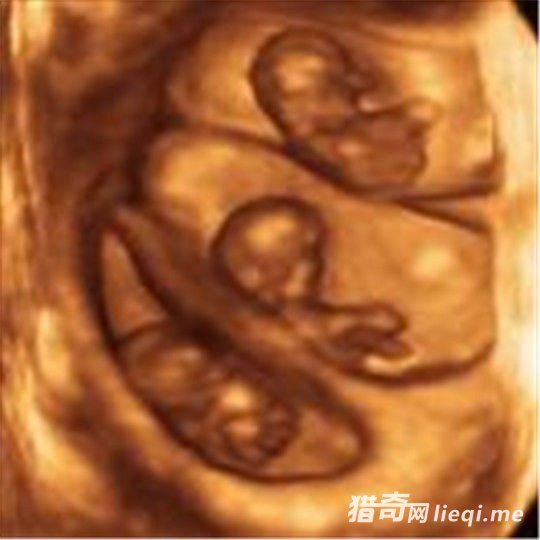

据报道称,在印度的苏拉特市,一名超级孕妇一次产下了十一名婴儿 ! 这到底是真的还是图中的照片经过了加工 ? 有知情人士表示,照片中的十一个婴儿确实都出生在同一天,也就是 2011 年的。